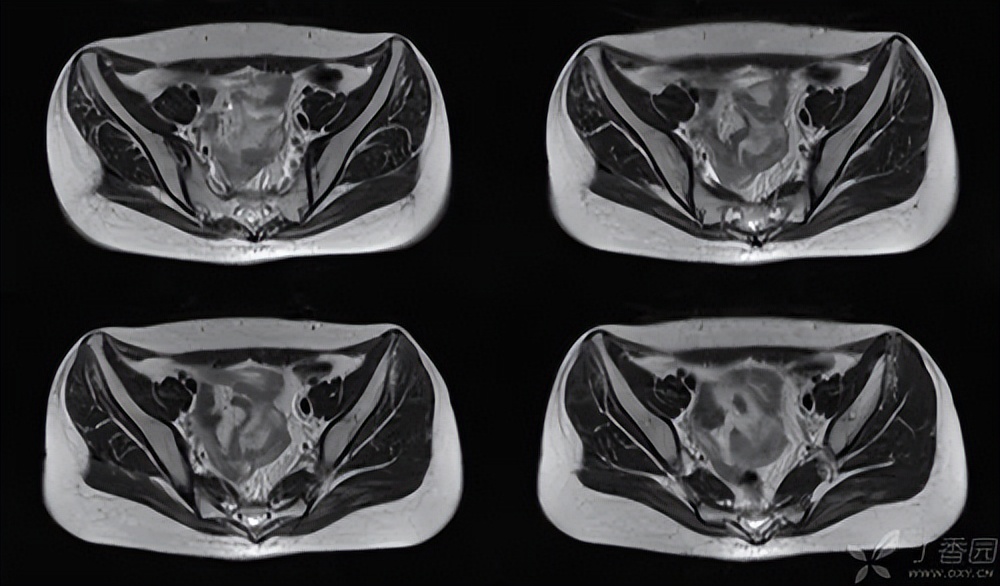

避免漏诊,对患者进行X线检查的同时完善CT检查,其可以显示出骶骨骨折和后环的移位不明显的骨折,还可以反映出骶骨的骨密度。

之后再行MRI检查,对67例患者进行研究发现CT检查诊断骶骨骨折的确诊率为74.6%,MRI的正确诊断率为100%。 使用MRI在骨盆前环骨折的患者中发现了骨盆后环损伤。